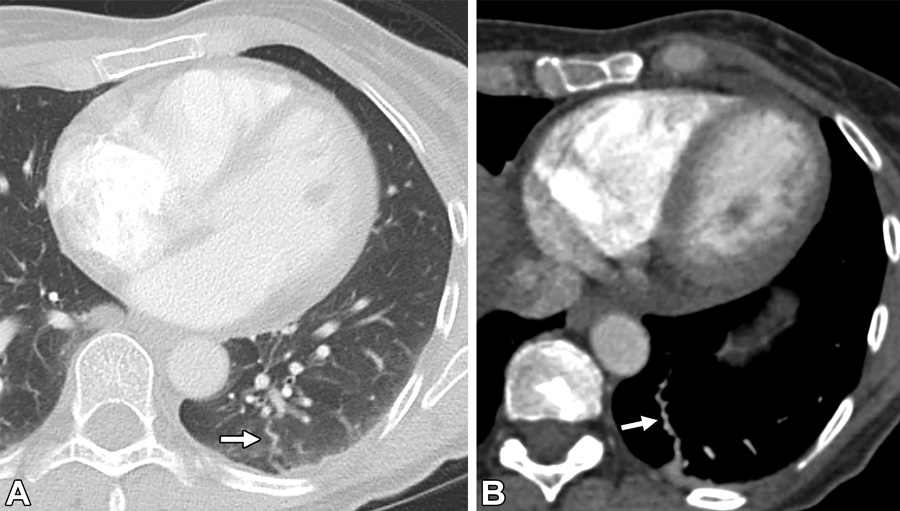

肺动脉假性动脉瘤。56岁男性,既往Swan-Ganz导管置入史。(A)轴位平扫CT图,右肺上叶圆形结构(白色箭头)。(B)轴位增强CT图,圆形血管结构(白色箭头),注意观察没有引流静脉。(C)冠状位最大密度投影图,此结构与邻近的肺动脉相连(白色长箭头),符合肺动脉假性动脉瘤(白色短箭头)表现。

肝肺综合征。72岁男性,气短。(A,B)按照肺栓塞扫描程序进行的轴位增强CT,可见双肺下叶扩张的胸膜下血管(黑色箭头),扩张的结节形及螺旋形血管(白色箭头)与胸膜相连。(C)上腹部CT图,可见肝表面呈结节状(白色虚线箭头),符合肝硬化表现。(D)轴位CT,可见左心房的右侧早期显影(白色星号),符合右向左分流表现。以上表现符合肝肺综合征。